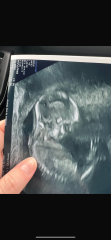

Im currently 16 weeks and 4 days pregnant and just had our gender scan and fetal well being check which went really well although baby wasn’t playing ball with getting a good picture, they’re face was facing my back so we could only see back of baby’s head mostly.

however after receiving the pictures the 3d/4d scan has absolutely terrified me and I wanted to see if this is normal at this stage! I appreciate they move a lot but it seems a chunk of their face is missing!

Terrified from 16 week sneak peek!

It's likely to just be image artefacts - fluid for example can make it look like there are holes or gaps in baby, and at 16 weeks there is a lot of fluid around baby!

Just read your post again - if their face was against your back, I suspect it's an image artefact from where the tissue of their face was leant up against fluid/womb/your back!